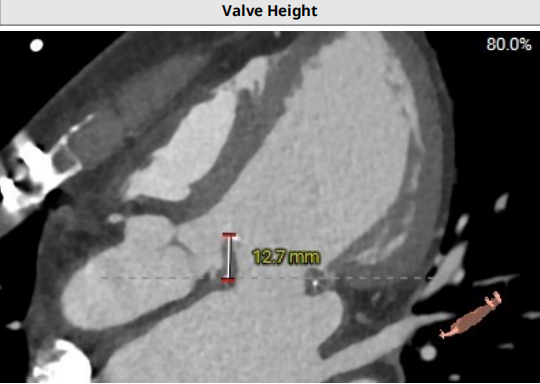

患者二尖瓣生物瓣换瓣术后:病史提供原生物瓣品牌epic 27号,生物瓣环呈环形细丝,两瓣脚稍有显示,生物瓣周长折算内径24.6mm,外径26.9mm,瓣架高度12.7mm:

术中建议投射角度RAO 64°/CAU 7°:

左心室和二尖瓣轴线角度153°:

主动脉-二尖瓣角度123°:

该患者原生物瓣狭窄伴有瓣叶脱垂,真实内径22.5mm,据此选择J-Valve 25mm瓣膜;